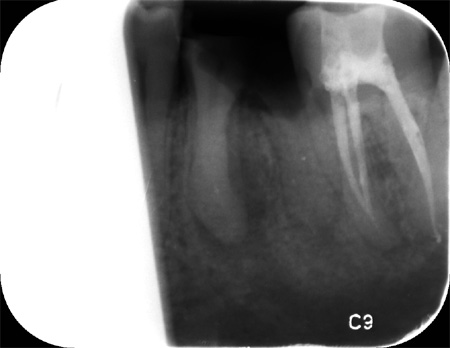

Dit was de foto die de tandarts padrao op 07-10-2021 ter beschiking had

Er is geen nieuwe foto tenminste geen begin foto gemaakt Element 36 is niet meer te behouden Deze foto is pas gemaakt nadat hij element 36 had weg gefreest en 37 was al geopend voor een wortel kanaal behandeling

Er zijn op de fotos ookop element 36 en 37 geen wortepunt onstekingen te zien

Toen ik zei dat het volgens mijn twee second opinions het de gewoonte was om detail foto te maken . Daarop zei de weledelgeleerde tandarts A Padrao dat hij dat ook had gedaan .Waarop ik zei dat hij dat had gedaan nadat de kies element 36 was weggefreest!!. Ook bij een second opinion zeg de betreffende tandarts:Hij kon er niets over zeggen er was geen beginsituatie . Daar waar het vraagteken staat er is geen beginfoto .